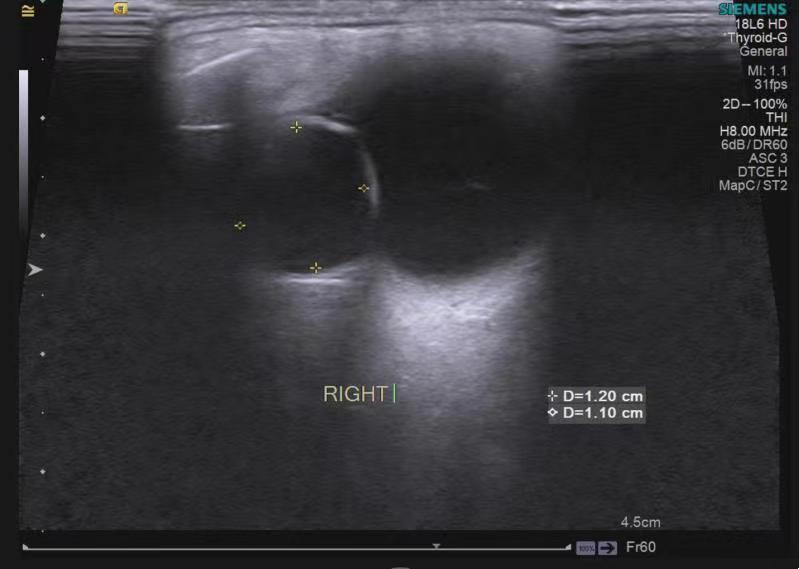

球囊顶住视网膜脱落部位

术后第二天黄斑OCT基本复位